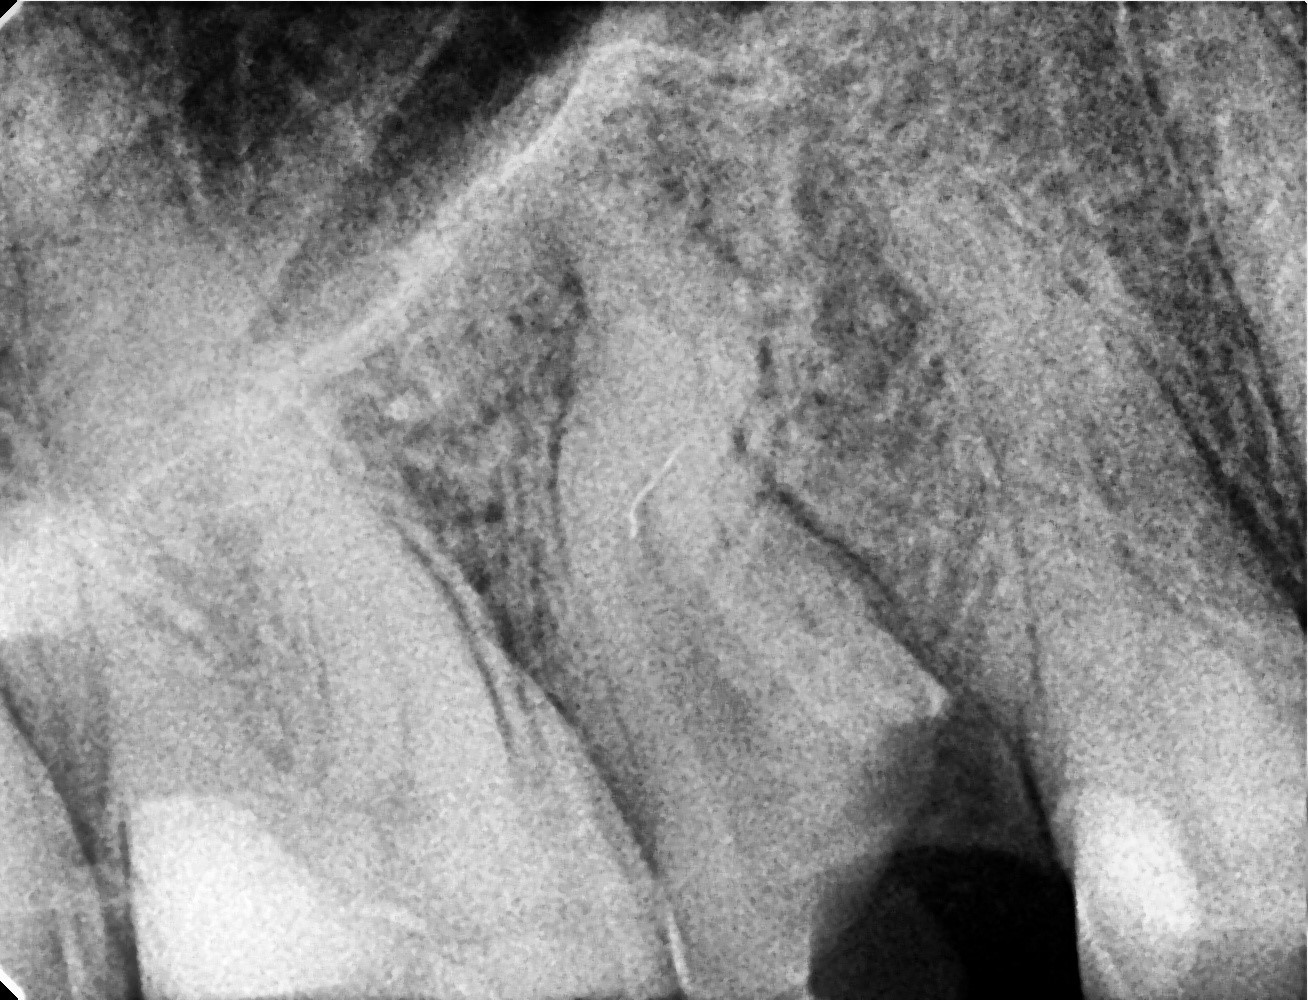

• In the palatal canal, the 10/07 “Opener” file from the SuperSystem Advanced Kit was used at 250 rpm and 1.5 Ncm torque, progressing to the middle third.

Following irrigation, 17/05 file was used at the same settings to reach the apex.

Working length was confirmed using a #06 K-file.

Canal enlargement was completed with the Perfect Advanced Kit 17/05 file (images 3 and 4).